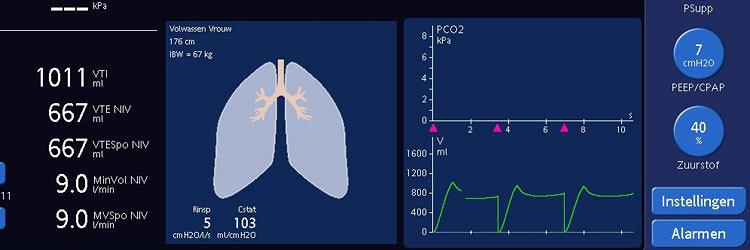

Non-invasieve positievedrukbeademing (NPPV) biedt mechanische ondersteuning van de respiratie via een non-invasieve interface op de bovenste luchtweg. Er zijn twee vormen: continuous positive airway pressure en bifasische positievedrukbeademing. Door de fysiologische effecten van extrinsieke peep kan atelectase worden opgeheven, wordt de hydrostatische druk van de longcapillairen verlaagd en kan dynamische hyperinflatie worden opgeheven, hetgeen kan leiden tot een betere ventilatie en oxygenatie. Toepassing van NPPV kan intubatie en sedatie voorkomen en de IC-ligduur verkorten. Progressie van respiratoir falen en onterecht uitstel van intubatie verhogen de mortaliteit. Juiste patiëntenselectie en nauwkeurige observatie van de effecten op de respiratie zijn dus nodig. Bij patiënten met een exacerbatie van COPD, cardiogeen longoedeem en bij immuungecompromiteerde patiënten met een pneumonie is toepassing van NPPV bewezen effectief. Het aantal intubaties en mortaliteit werd door toepassing van NPPV significant gereduceerd.